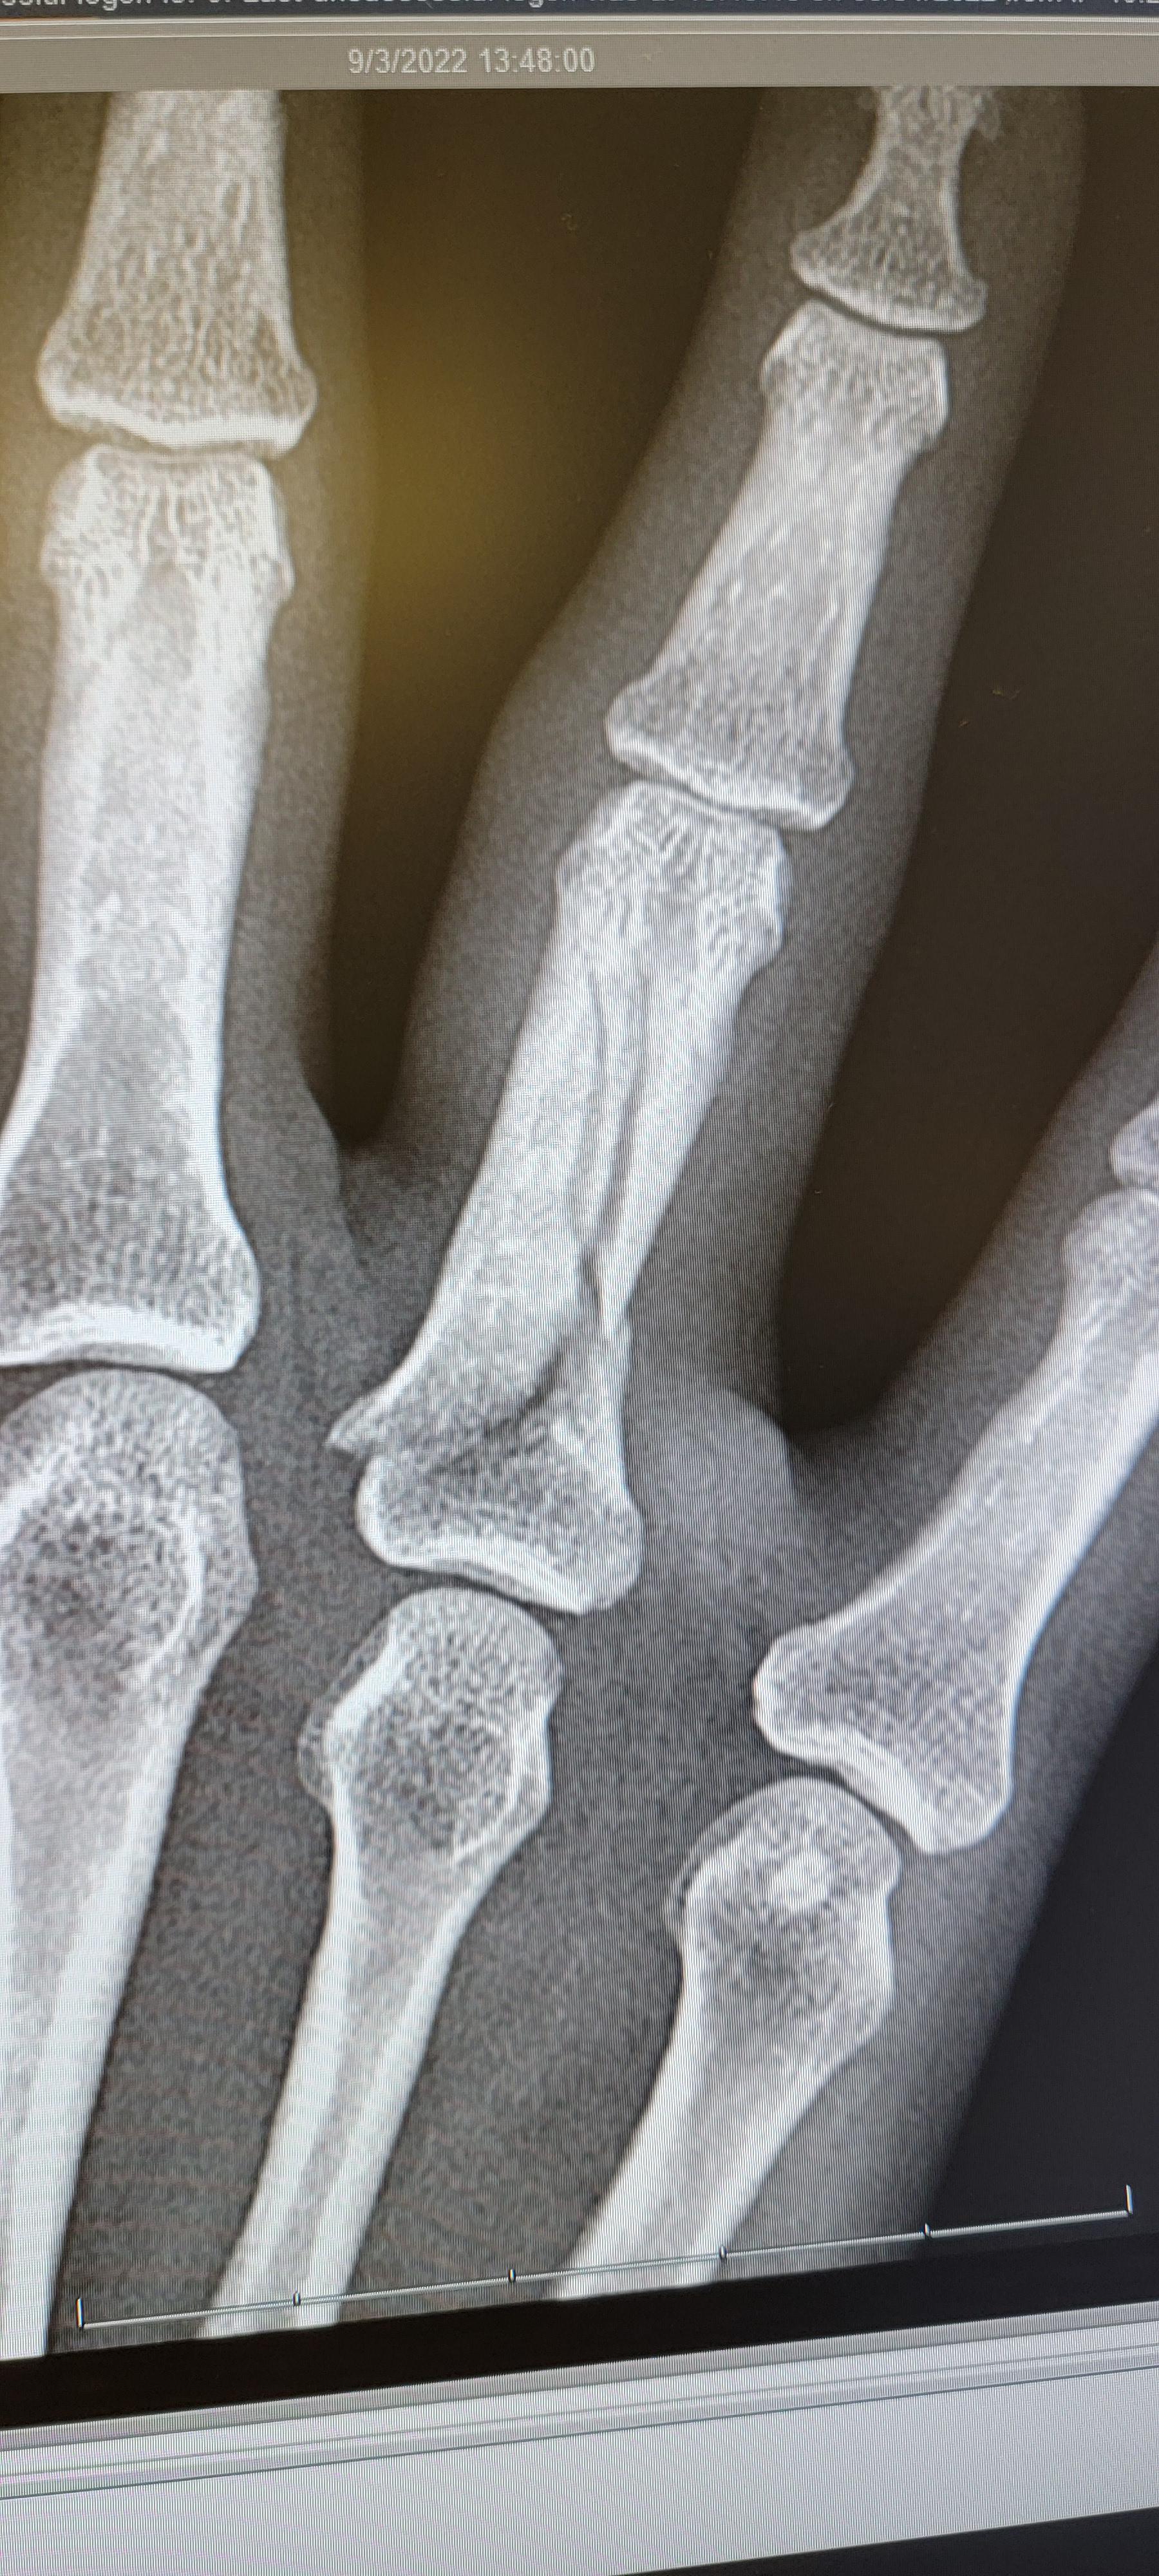

dog bite fractured finger r/ThatsInsane Finger Is Numb After Dog Bite If a finger can't be bent after a dog bite, seek medical attention immediately. These three include (1) axonotmesis; Dogs cause most of the animal bites that. You lose feeling in the area near the bite, or it feels numb or tingly. The skin near the bite turns cold or pale or it changes colour. There are three different categories. Finger Is Numb After Dog Bite.